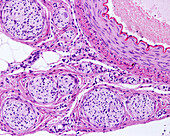

13742427 - Elastic artery, light micrograph

13742425 - Elastic arteries, light micrograph